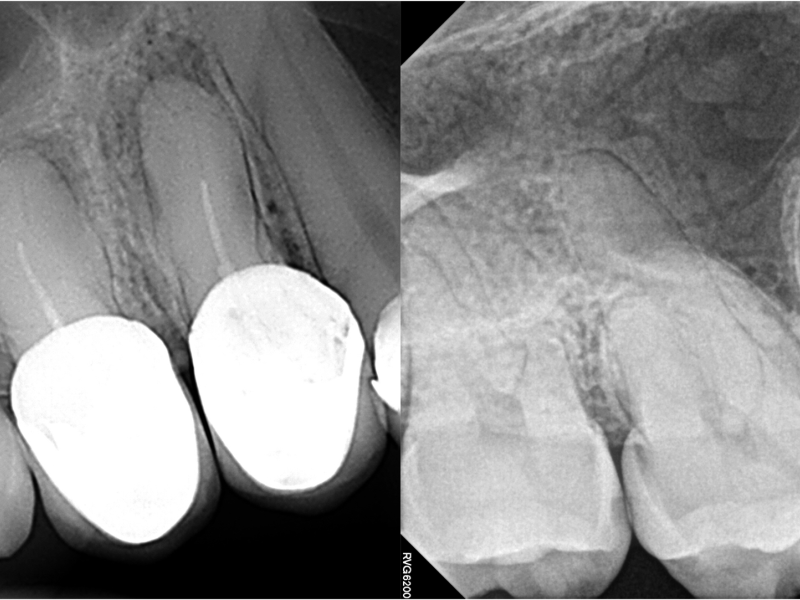

Nestor Cohenca, DDS, FIADT